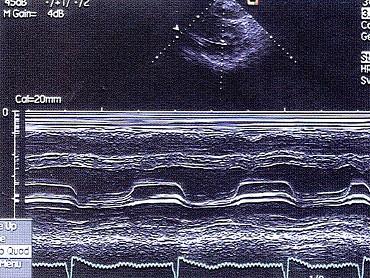

问题 该M型图提示?(?)

选项 A.风湿性心脏病二尖瓣狭窄 B.高血压心脏病 C.左房黏液瘤 D.扩张型心脏病 E.肥厚性心肌病

答案 A